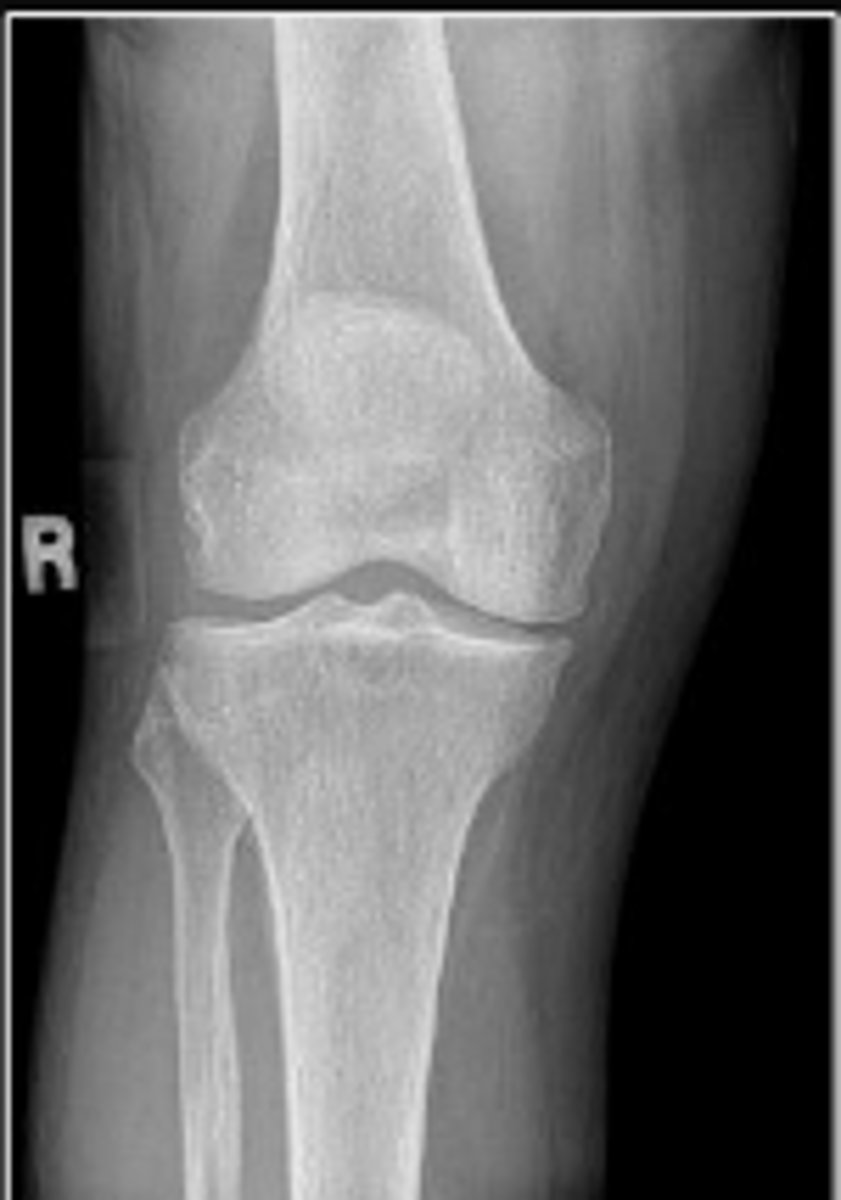

Right AP knee

What is the name of the radiographic view?